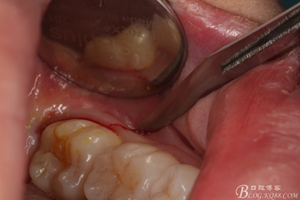

圖1.術(shù)前的口內(nèi)照片:38未萌出、牙齦輕度紅腫,37遠中有盲袋。